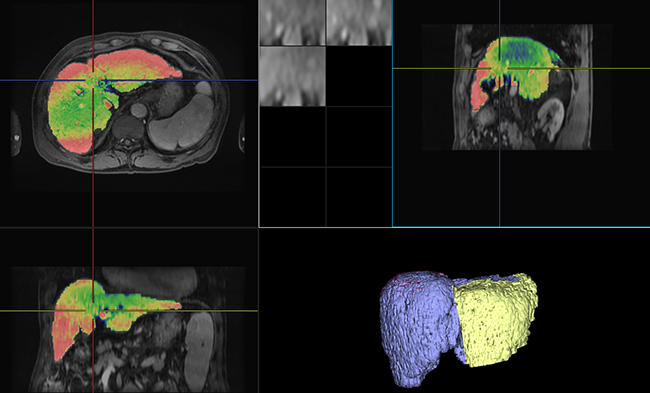

Úng dụng trích xuất gan và các vùng mạch gần đó từ hình ảnh chụp CT tăng cường chất cản quang và hiển thị kết quả dưới dạng hình ảnh được ánh xạ 3D. Mô phỏng thủ thuật cắt bỏ gan cũng được đề cập.

Úng dụng để phân tích chức năng gan. Phần mềm hiển thị hình ảnh chụp MR có tăng cường chất cản quang ở nhiều pha và hình ảnh tham chiếu. Kết quả được tính toán và trình bày cho các vùng gan và lá lách.

Ứng dụng phân tích dòng máu của các cơ quan ở bụng theo thời gian, bao gồm tuyến tụy. Thể tích máu mô (TBV), lưu lượng máu mô (TBF), thời gian chuyển tiếp trung bình (MTT) và thời gian đạt đỉnh (TTP) được tính toán.